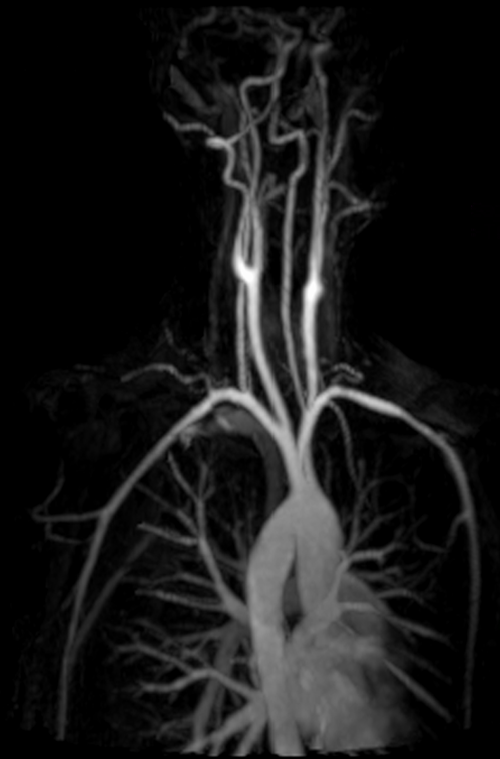

mri subclavian arm down mip 3 - MRI